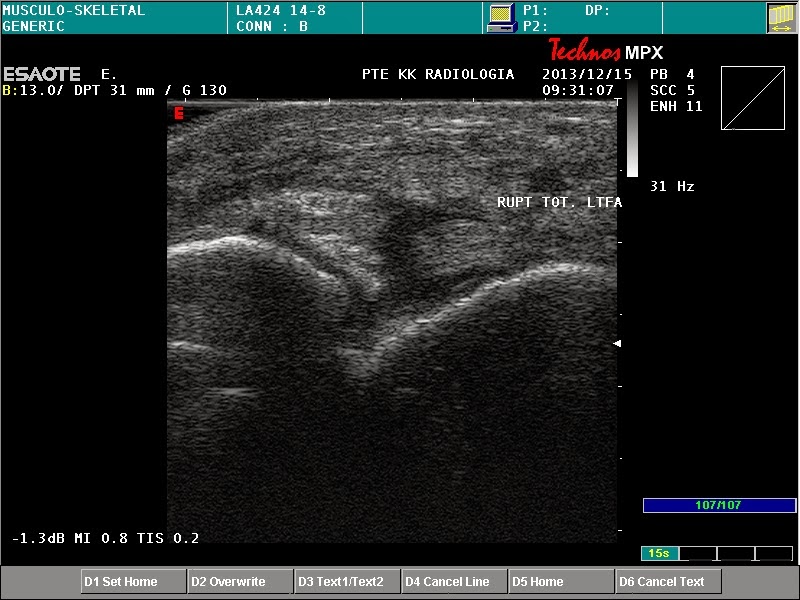

Rupture of the talofibuar ligament Szerző: admin | dec 15, 2013 | MSK | Nincsenek hozzászólások the ruptured LTFA is surrounded by mild hypoechogen area (haematoma) haematoma around the ruptured LTFA normal thickness and structure of LTFA Technos MPX is back!